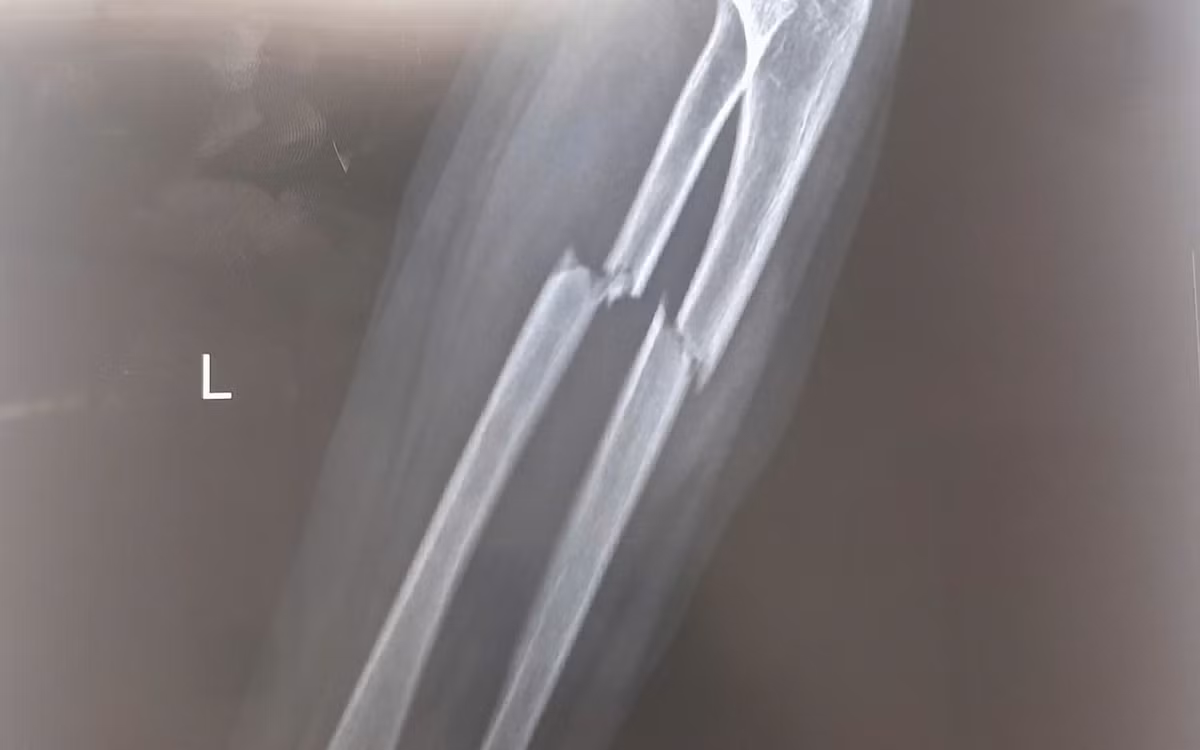

Phẫu thuật kết hợp xương cố định xương gãy, phục hồi vận động sớm - Ảnh BVCC

Sau hơn 1 giờ phẫu thuật, dưới sự hỗ trợ của hệ thống máy C-arm, ê-kíp phẫu thuật tiến hành nắn chỉnh trục xương giúp đưa hai đầu xương gãy và mảnh xương di lệch về đúng vị trí giải phẫu, khôi phục chiều dài và chức năng sấp, ngửa của cẳng tay.

Sau đó, phẫu thuật viên đặt nẹp vít cố định nhằm giữ vững hai đoạn xương, tạo điều kiện cho quá trình liền xương diễn ra đúng vị trí giải phẫu, tránh nguy cơ sai lệch hoặc biến dạng. Toàn bộ quá trình phẫu thuật được thực hiện qua một đường mổ nhỏ ở phía trước. Chỉ với một đường tiếp cận này, phẫu thuật viên có thể nắn chỉnh và cố định đồng thời cả hai xương gãy, giúp giảm tổn thương phần mềm, hạn chế mất máu và giảm đau sau mổ cho bệnh nhi.